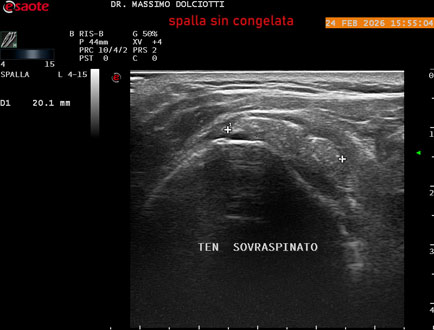

Data inserimento: 02/03/2026

Ecografia del: 24/02/2026

Strumento: Esaote MyLab Eight

Sonda: Lineare Multifrequenza 4-15 MHz

Età Paziente: F 71 anni

Motivazione dell'esame: da 1 mese dolore alla spalla sinistra, anche di notte.

Commento all'esame: le immagini ed il video documentano il tendine sovraspinato sinistro spiccatamente disomogeneo, per presenza di immagine iperecogena, delle dimensioni di 21 x 4 mm, da ricondurre a estesa calcificazione. Quadro clinico di spalla congelata.

Conclusioni: spalla sinistra congelata (frozen left shoulder).